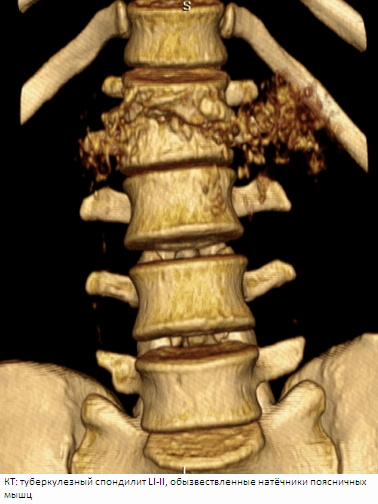

Использование КТ (компьютерной томографии) позволяет уточнить степень и характер поражения костной ткани, в том числе дуг и отростков позвонков, что невозможно при традиционной рентгенографии, а также выявит костную деструкцию с секвестрами на ранних стадиях. Таким образом, использование КТ при туберкулезном спондилите показано: в случаях, когда на обычных рентгенограммах и томограммах деструкция не выявляется, а на МРТ имеется патологическое изменение сигнала от позвонков; для выявления или уточнения деструкции костных элементов задней позвоночной колонны (дуг, отростков, дугоотростчатых суставов); для уточнения характера разрушений в сложных для рентгенологического исследования областях - субокципитальной, шсйно-грудной, пояснично-крестцовой; при недостаточности рентгенологической информации о соотношении деструктивных костных полостей с просветом позвоночного канала, паравертебральными тканями и соседними органами; в послеоперационном периоде для оценки сращения трансплантатов с костным ложем, радикальности выполненного оперативного вмешательства и выявления рецидивов паравертебральных абсцессов.

Инфильтрация в позвоночном канале выявлялось у 45(32,1 %) больных. На рентгенограммах абсцессы хорошо выявлялись в грудном отделе позвоночника, где они видны на фоне воздушной легочной ткани. Забрюшинные абсцессы выявлялись по косвенному признаку расширения контуров m.iliopsoas major, когда достигали значительных размеров. Невозможно было увидеть абсцесс мягких тканей спины и небольшие паравертебральные абсцессы в поясничном отделе позвоночника. Контуры абсцессов и их соотношения с окружающими органами на рентгенограммах и томограммах удавалось определить не всегда. КТ и МРТ в равной степени хорошо выявляли абсцессы, их камеры, соотношения с позвонками и окружающими органами и тканями, особенно после внутреннего контрастирования. На ранней стадии формирования абсцесса отмечалась инфильтрация жировой прослойки вокруг тела позвонка. Преимущество МРТ — возможность многопроекционного исследования, что позволяло выявить соотношения абсцессов не только с окружающими тканями, но и связь их между собой. Комплексная оценка изменений костной структуры, выявляемых на рентгенотомограммах и КТ, и патологических изменений сигнала на МРТ, давала представление о морфологических изменениях в позвоночнике и о фазе туберкулезного спондилита.